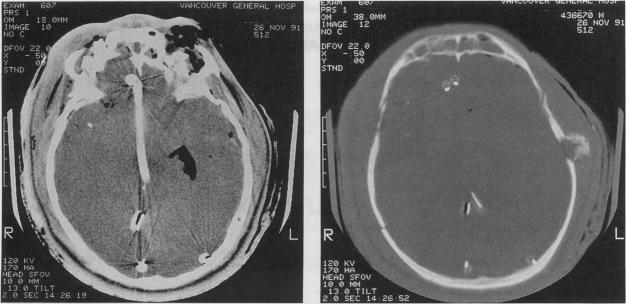

Inadvertent intracranial placement of a nasogastric tube in a patient with severe head trauma.

Department of Radiology, Vancouver General Hospital, BC.

CMAJ. 1992 Sep 1;147(5):668-9.

https://cdn.ncbi.nlm.nih.gov/pmc/blobs/8370/1336388/d365c8ec1901/cmaj00258-0107-a.jpg

https://cdn.ncbi.nlm.nih.gov/pmc/blobs/8370/1336388/1e3bb4947d0e/cmaj00258-0106-a.jpg

https://cdn.ncbi.nlm.nih.gov/pmc/blobs/8370/1336388/9d82bf11c926/cmaj00258-0106-b.jpg